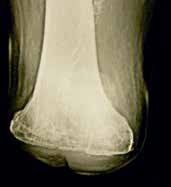

Falls die Haut trotz Kniescheibenentfernung immer noch unter starker Spannung steht, ist auch eine höhere Amputation im Sinne einer transkondylären Amputation möglich. Diese Amputationshöhe zeigt ebenfalls eine annähernd volle Belastbarkeit durch die breite Auflagefläche nach der Regel Druck = Kraft/Fläche. Dabei ist darauf zu achten, dass die Schnittfläche etwas nach lateral ansteigt. Dies ist deshalb notwendig, weil das Femur physiologisch in einer leichten Adduktionsstellung steht, bei der Operation durch die entspannte Muskulatur, verursacht durch die Narkose, allerdings diese Adduktion nicht vorliegt. Legt man dann die Schnittebene einfach quer zur vermeintlichen Oberschenkelachse an, würde daraus bei wiederum normaler Spannung der Muskulatur nach der OP eine tiefere Stellung des lateralen Kondylus resultieren. Die Ecken der Schnittfläche werden nur gering abgerundet, um spätere Druckstellen zu vermeiden. Eine transkondyläre Amputation ist bis zum Übergang in die Femurdiaphyse möglich.

Eine zu hohe Weichteilspannung kann man durch Entfernung der Kniescheibe, eine eventuelle transkondyläre Nachamputation oder auch durch eine suprakondyläre Verkürzungsosteotomie (nur bei nicht durchblutungsgestörten Patienten) operativ behandeln (Abb. 9 u. 10). Letztere sind immer wieder von Seiten der Orthopädie-Technik als primäre Operation bzw. Lösung nachgefragt. Sie sind jedoch primär Einzelfällen (ohne Durchblutungsstörungen) und Problemfällen vorbehalten, weil es im Rahmen der Verkürzung ebenfalls zu einer deutlichen Störung der muskulären Situation kommt, da sich die Weichteile „zusammenschieben“ und es dadurch zu einer Kraftminderung in der Führung des Restbeines kommt – zumindest vorübergehend, teilweise auch längerfristig.